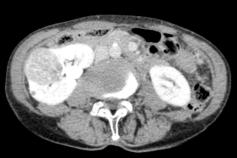

廣泛開展腹腔鏡下腎癌根治術(shù)、腎盂癌根治術(shù)、腎部分切除術(shù)、腎腫瘤剜除術(shù)、腎上腺腫瘤切除術(shù)、腎盂輸尿管成形術(shù)、腎囊腫去頂減壓術(shù)、輸尿管上段切開取石術(shù)等。全腔鏡下進(jìn)行,創(chuàng)傷小、恢復(fù)快。

腹腔鏡腎腫瘤剜除術(shù)(保腎) 腹腔鏡腎癌根治術(shù) 腹腔鏡腎盂癌根治術(shù)